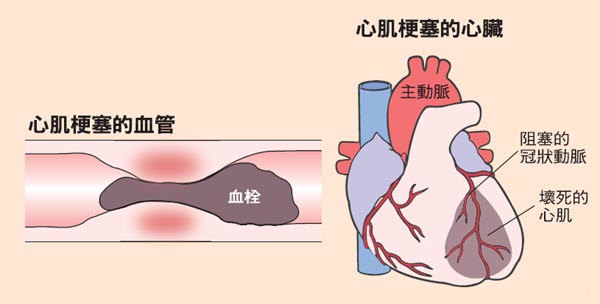

急性心肌梗死是冠状动脉急性、持续性缺血缺氧所引起的心肌坏死,是最危重的心血管疾病。其特点是发病急、进展快、病情重,在数分钟内即可发展为心脏呼吸骤停,甚至死亡。急性心肌梗死的常见诱因有便秘、大量饮酒、寒冷刺激、暴饮暴食、过度劳累、情绪激动等。

室颤也就是我们经常说的心室颤动。因为心室的肌肉快速而微弱地进行收缩,从而造成不协调的乱颤,从而导致心脏没有及时排血,会导致心音和脉搏的消失。因此在出现室颤以后,患者需要及时进行治疗,这是导致患者死亡的最重要原因,并且患者在死亡之前还会有循环衰竭的情况出现。